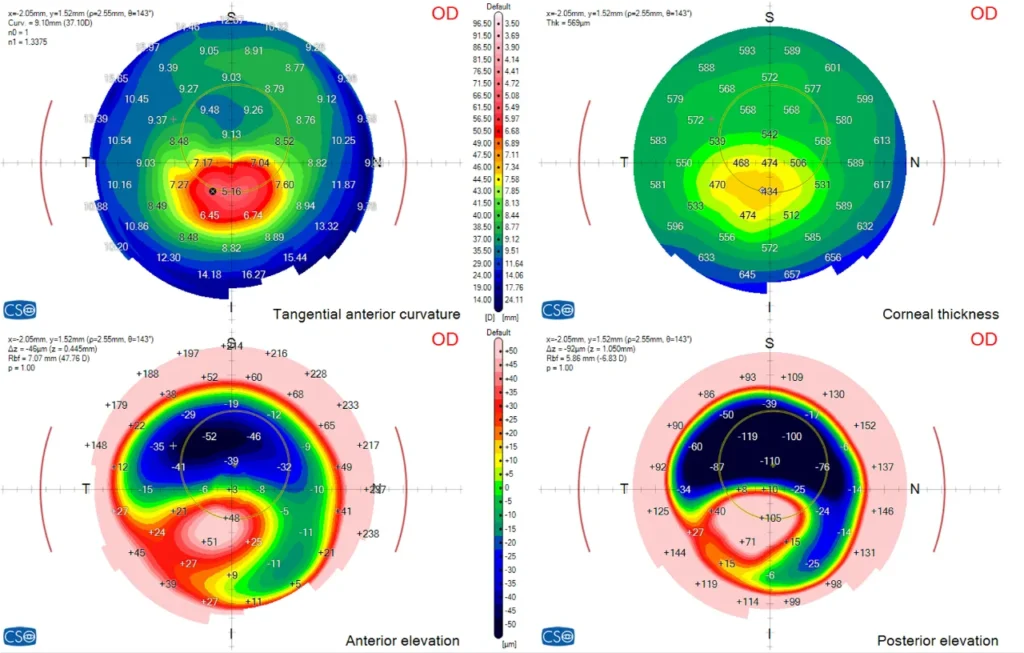

Die Pentacam erfasst mit einer rotierenden Kamera ein 3D-Bild Ihrer Hornhaut und misst ihre Form und Dicke an Tausenden von Punkten. So können wir Keratokonus in einem sehr frühen Stadium erkennen - auch wenn die Sehkraft noch normal erscheint.

Das MS-39 kombiniert Hornhauttopographie mit hochauflösender OCT (optische Kohärenztomographie). Es liefert uns ein extrem detailliertes Bild der Hornhautschichten, mit dem wir subtile strukturelle Veränderungen erkennen und ein Fortschreiten im Laufe der Zeit überwachen können.

Dank neuester Technologien sind wir heute in der Lage, sowohl die vordere als auch die hintere Oberfläche der Hornhaut mit extrem hoher Präzision zu messen. Dank dieser verbesserten Genauigkeit können Anomalien bereits in sehr frühen Stadien erkannt werden, was zu schnelleren und zuverlässigeren Diagnosen führt. Erkrankungen wie Keratokonus oder Pellucid Marginal Degeneration (PMD) lassen sich nun deutlich früher als bisher diagnostizieren, was die Patientenergebnisse verbessert und eine rechtzeitige Behandlung ermöglicht.

Darüber hinaus bietet diese Technologie ein zusätzliches Mass an Sicherheit bei der Augenlaserchirurgie. Da sie eine viel präzisere Beurteilung der Hornhaut ermöglicht, können wir mit grösserer Sicherheit feststellen, ob ein Patient ein geeigneter Kandidat für Verfahren wie LASIK oder PRK ist, was das Risiko von Komplikationen deutlich verringert.

Die moderne OCT-Technologie für den vorderen Augenabschnitt bietet eine ultrahochauflösende Darstellung des Hornhautgewebes und ermöglicht eine unglaublich detaillierte Visualisierung seiner Struktur. Dieses Mass an Präzision ist ein grosser Vorteil bei der Nachsorge von Hornhauterkrankungen und der postoperativen Überwachung. Sie ermöglicht es den Ärzten, subtile Veränderungen der Hornhaut im Laufe der Zeit mit grosser Genauigkeit zu verfolgen.

Einer der wichtigsten Vorteile dieser Bildgebung ist die Möglichkeit, Hornhautnarben nicht nur hinsichtlich ihres Vorhandenseins, sondern auch ihrer Tiefe und Ausdehnung innerhalb der Hornhautschichten zu beurteilen. Solche detaillierten Informationen sind entscheidend für die Bewertung der Auswirkungen auf die Sehqualität und für die Planung künftiger Behandlungsstrategien, falls erforderlich.